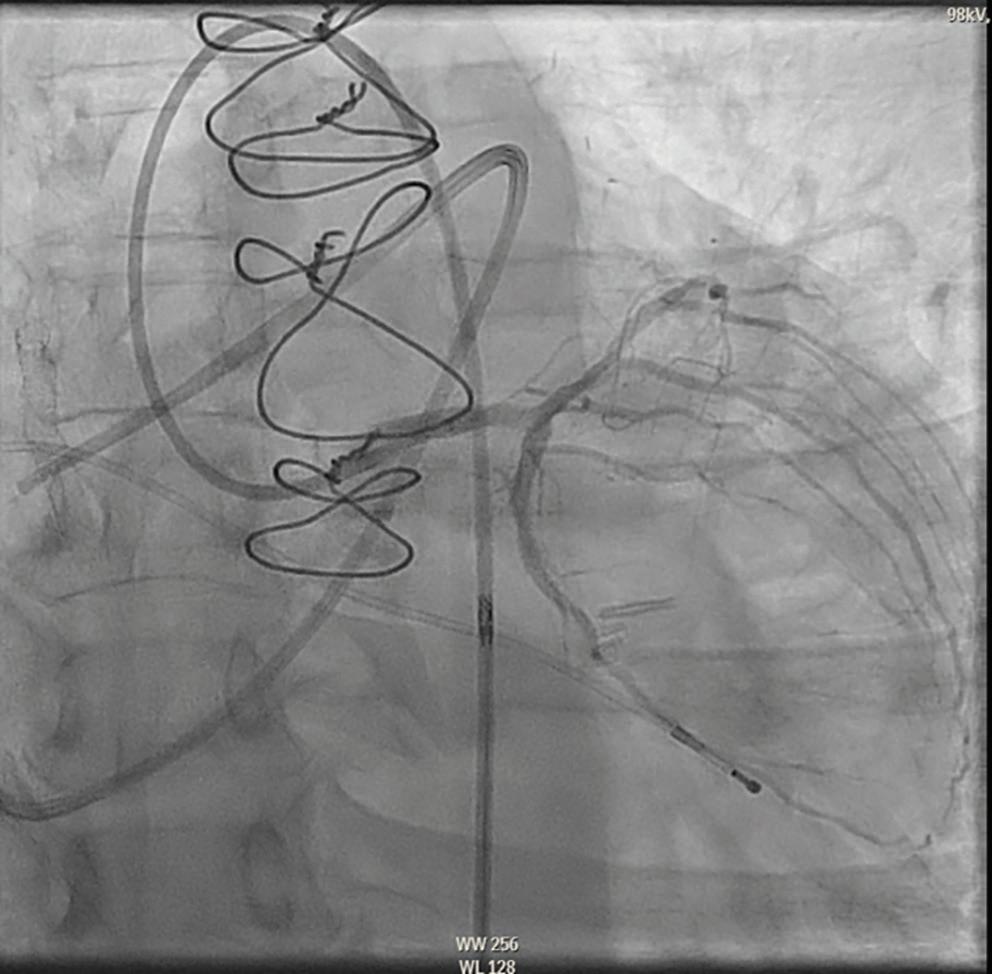

AMI-CS with Misidentification of the Culprit Requiring Delayed Revascularization of LCX, Complicated by MR Requiring IABP and MV TEER

A 63-year-old man with a coronary artery bypass graft performed in 2008 (left internal mammary artery-left anterior descending [LIMA-LAD], selective saphenous vein graft-right coronary artery [SVG-RCA]) presented to an outside facility with chest pain and was found to have an inferior ST-elevation MI (STEMI). He was taken to the cath lab. The left main coronary artery was patent and the LAD was occluded in the mid segment, with a patent LIMA-LAD perfusing the mid-distal LAD. The left circumflex artery (LCX) had an 80% proximal lesion and was not grafted. The right coronary artery (RCA) was occluded in the proximal segment, and the SVG-RCA graft was also occluded proximally. The culprit was thought to be the SVG-RCA. The patient was loaded with dual antiplatelet therapy and started on eptifibatide. Three stents were implanted in the SVG-RCA. On hospital day (HD) 3 the patient continued to have chest pain with ST elevations, and he returned to the cath lab. The SVG-RCA graft was found

to be re-occluded within the stents and the prior LCX 80% lesion was noted to progress to a 100% occlusion.

The patient was transferred to our institution for further management on HD 4. He arrived with a heart rate of 60 BPM and blood pressure 110/80 mmHg. O2 saturation was 97%, and he was in respiratory distress requiring bilevel positive airway (BiPAP) ventilation. Creatinine was 2 mg/ dl, alanine transaminase 249 U, bilirubin 1.7 mg/dl, and lactate 3 mmol/l. A transthoracic echocardiography (TTE) was performed that showed a left ventricular ejection fraction of 40% with inferior and posterior hypokinesis and moderate, posteriorly directed mitral regurgitation (MR). Review of the outside angiogram suggested that the SVG-RCA occlusion may have been chronic given the appearance of the SVG thrombus and that the culprit of the STEMI presentation was the LCX lesion given the acutely

Figure 1A Figure 1B

A: Left circumflex artery pre-percutaneous coronary intervention.

B: Left circumflex artery post-percutaneous coronary intervention.

progressing lesion. The patient continued to have active chest pain requiring nitroglycerin.

The patient was taken back to the cath lab for revascularization of the LCX with one drug-eluting stent, with 0% residual lesion and thrombolysis in MI (TIMI) grade 3 flow. A pulmonary artery line was inserted which showed right atrium pressure of 20 mmHg, right ventricle 55/20 mmHg, pulmonary artery 55/24/32 mmHg, pulmonary capillary wedge 24 mmHg with V waves to 40, and Fick CI of 1.7 l/min/m2. Given significant respiratory distress that was thought to be related to MR, potentially underestimated on TTE given the eccentric nature and tall V waves, an intra-aortic balloon pump (IABP) was inserted. The patient returned to the cardiac care unit with resolution of chest pain and significant respiratory improvement. Transesophageal echocardiography (TEE) was performed, which showed severe, eccentric posteriorly directed MR in the setting of inferolateral hypokinesis. Given significant respiratory distress requiring BiPAP in the setting of severe MR with inability to liberate from IABP despite high doses of IV vasodilators, the patient returned to the cath lab on HD 12 for mitral valve (MV) transcatheter edge-to-edge repair. The patient

underwent successful implantation of a MitraClip G4 XTW with reduction of MR to trace. The next day, the patient was weaned from both BiPAP and the IABP. The patient was transferred to the floor and guideline-directed medical therapy was instituted. On HD 18, the patient was discharged to home.

There are several lessons from this case. First, appropriate revascularization, even if delayed, remains standard of care for acute MIcardiogenic shock (AMI-CS). In the present case, the culprit was initially misidentified as the SVG-RCA graft, and the acute culprit lesion was the LCX, which eventually underwent revascularization 5 days later. Second, IABP should not be considered as a routine strategy for AMI-CS. However, in this case, given severe ischemic MR with respiratory distress, a trial of IABP was pursued and led to significant improvement on the cath lab table. Had the patient significant hypotension, or if IABP had not led to improvement, escalation would have been made to an Impella CP. Third, in select patients with CS with severe MR, MV transesophageal echocardiography can be considered in an attempt to liberate from mechanical circulatory support.

Figure 1C Figure 1D

C: Mitral valve with severe mitral regurgitation prior to transcatheter edge-to-edge repair.

D: Mitral valve with mild mitral regurgitation after mitral transcatheter edge-to-edge repair.